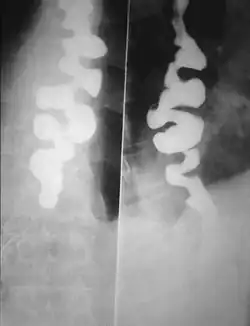

Lo spasmo esofageo diffuso, chiamato anche pseudodiverticolosi spastica, esofago a cavaturaccioli, esofago a corona di rosario è una discinesia dell'esofago.

Va effettuata con manometria e RX con pasto baritato in cui si vede il tipico aspetto a cavatappi che dà anche il nome alla patologia.